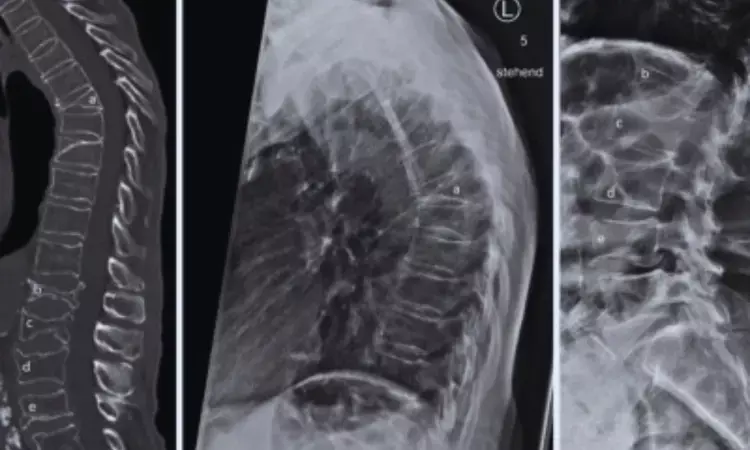

Bone loss is a well-recognized challenge of prolonged exposure to microgravity. Astronauts experience accelerated skeletal deterioration, especially in weight-bearing regions such as the spine and hip. To monitor and mitigate these effects, NASA routinely performs preflight and postflight dual-energy x-ray absorptiometry (DEXA) scans. While BMD provides information on bone quantity, TBS—derived from DEXA images—offers insight into trabecular bone microarchitecture, an important determinant of bone strength and fracture risk.

In the analysis, researchers evaluated DEXA scans from 51 astronauts who completed approximately six-month missions aboard the International Space Station (ISS). The cohort included 41 men and 10 women, ranging in age from the late 30s to mid-50s. Participants were grouped based on the countermeasures available during their missions: those who flew before the introduction of the advanced resistive exercise device (ARED), those with access to ARED, and those who used ARED in combination with bisphosphonate therapy. ARED is designed to simulate weightlifting in microgravity and has become a cornerstone of in-flight exercise programs.

- This study represents the first use of trabecular bone score to assess spaceflight-related changes in lumbar spine trabecular integrity.